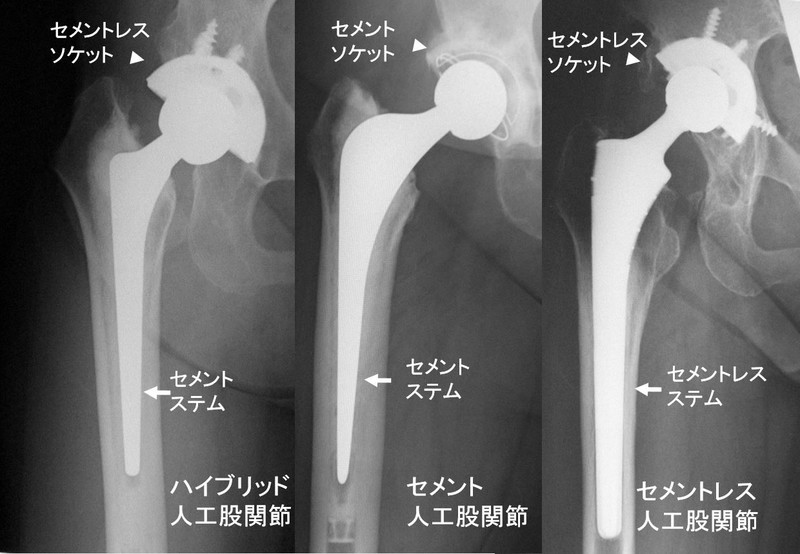

手術に用いる人工関節は、現在主に下記の3つのタイプが用いられています。

・ハイブリッドのタイプ(人工関節のソケットはセメントを使わずにスクリューで止め、表面を金属加工して骨が入るようにし、ステムは固定のためにセメントを使う)(写真左)

・ソケットとステムどちらもセメントを使うタイプ(写真中央)

・ソケットとステムどちらもセメントを使わないタイプ(写真右)

世界的に初期はセメントを使う手術が主流でしたが、現在はセメントを使わないタイプが多くなってきています。アメリカではほぼセメントを使用しておらず、日本の手術件数のうち8割ほどは使用していません。

また、セメントを使わないタイプは、骨が人工関節の金属表面に侵入して、固定が完成しますが、多少の期間を要します。

人工関節の固定にセメントを使うと、入った瞬間から骨に固定され、早期から全荷重可能ですが、きちんと医療側の指導のもとで行ってください。